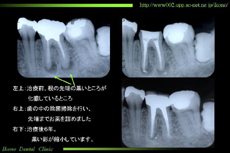

歯周病とは歯周病原菌(歯や歯茎に付着した細菌)や「噛み合わせ」などが原因で、歯周組織(歯を支えている歯肉や顎の骨)が破壊される病気です。なんと成人の約8割がかかっているといわれています。もちろん放置していて治るものではありません。骨にまで炎症がひろがると、骨がとけて歯が抜け落ちてしまうことがあるのです。事実、歯が失われる原因の約45%が歯周病によるものという調査結果もでています。最近では、この歯周病を生活習慣病の一つとして捉えられています。

正常な歯と歯周組織のX線写真 健康な歯肉 歯周病のX線写真

クリックで拡大されます